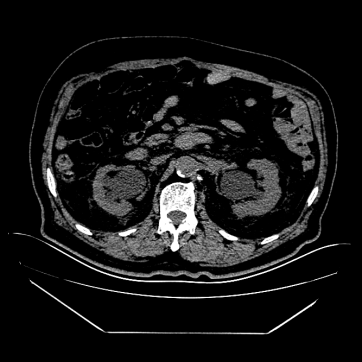

79 岁的王爹爹因「发现肾功能不全 9 天,双下肢水肿 2 天」入院,尿潴留合并多种慢性基础性疾病,留置尿管导出尿量约 1000 ml。经过一周住院治疗,爹爹的肾功能有所改善,但因尿潴留导致肾脏慢性损伤,留下了肾功能减退的遗憾。